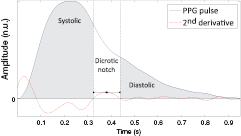

In the second step, the PPG pulse is separated into systolic and diastolic phases. The systolic phase, primarily associated with the ventricular ejection, was defined as the portion between the onset of the PPG pulse and the dicrotic notch. The diastolic phase, resulting from the reflections and re-reflections of the main PPG pulse in the systemic vascular network, was defined as the portion of the PPG pulse between the dicrotic notch and the pulse offset. The two phases of the PPG pulse are illustrated in figure 3.

Figure 3. Representation of the systolic and diastolic phases of the PPG pulse based on the detection of the notch (inflection) onset and offset.